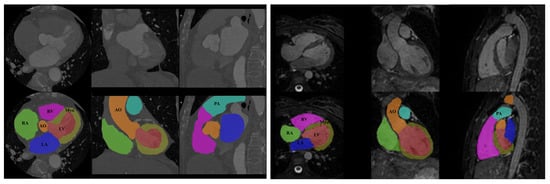

The network presented in the previous section was applied to the whole heart segmentation task and is evaluated on a dataset provided by Multi-Modality Whole Heart Segmentation Challenge (MM-WHS) organized by MICCAI []. The MM-WHS dataset consists of 60 cardiac CT/CTA and 60 cardiac MRI volumes, whereas 20 volumetric images include corresponding ground truths, manually labeled by two clinical experts. In contrast, the remaining 40 volumetric images are used for testing purposes. Ground truths of the testing dataset are provided in encrypted form and can be decoded to evaluate algorithms using the procedure described in []. The data were collected on patients from the everyday clinical environment, and it has a various quality to preserve the robustness of the developed algorithms when it comes to real clinical usage. The cardiac CT/CTA data are obtained using 64 slice CT scanners using a standard coronary CT angiography protocol, and cardiac MRI data were acquired using a navigator-gated 3D balanced steady-state free precession (b-SSFP) sequence for free-breathing whole heart imaging. The axial slices’ in-plane resolution is mm, and the average slice thickness is mm. The data include the following seven structures of the heart: (1) the left ventricle blood cavity (LV), (2) the right ventricle blood cavity (RV), (3) the left atrium blood cavity (LA), (4) the right atrium blood cavity (RA), (5) the myocardium of the left ventricle (Myo), (6) the ascending aorta (Ao), which is defined as the aortic trunk from the aortic valve to the superior level of the atria, and (7) the pulmonary artery (PA). An example of one slice from the used dataset is shown in Figure 3.

Figure 3.

An example of one slice with corresponding ground truth from 3D volume across axial, coronal, and sagittal planes. The ground truths include seven heart structures: LV (red), RV (magenta), LA (blue), RA (green), Myo (yellow), Ao (orange), and PA (cyan).